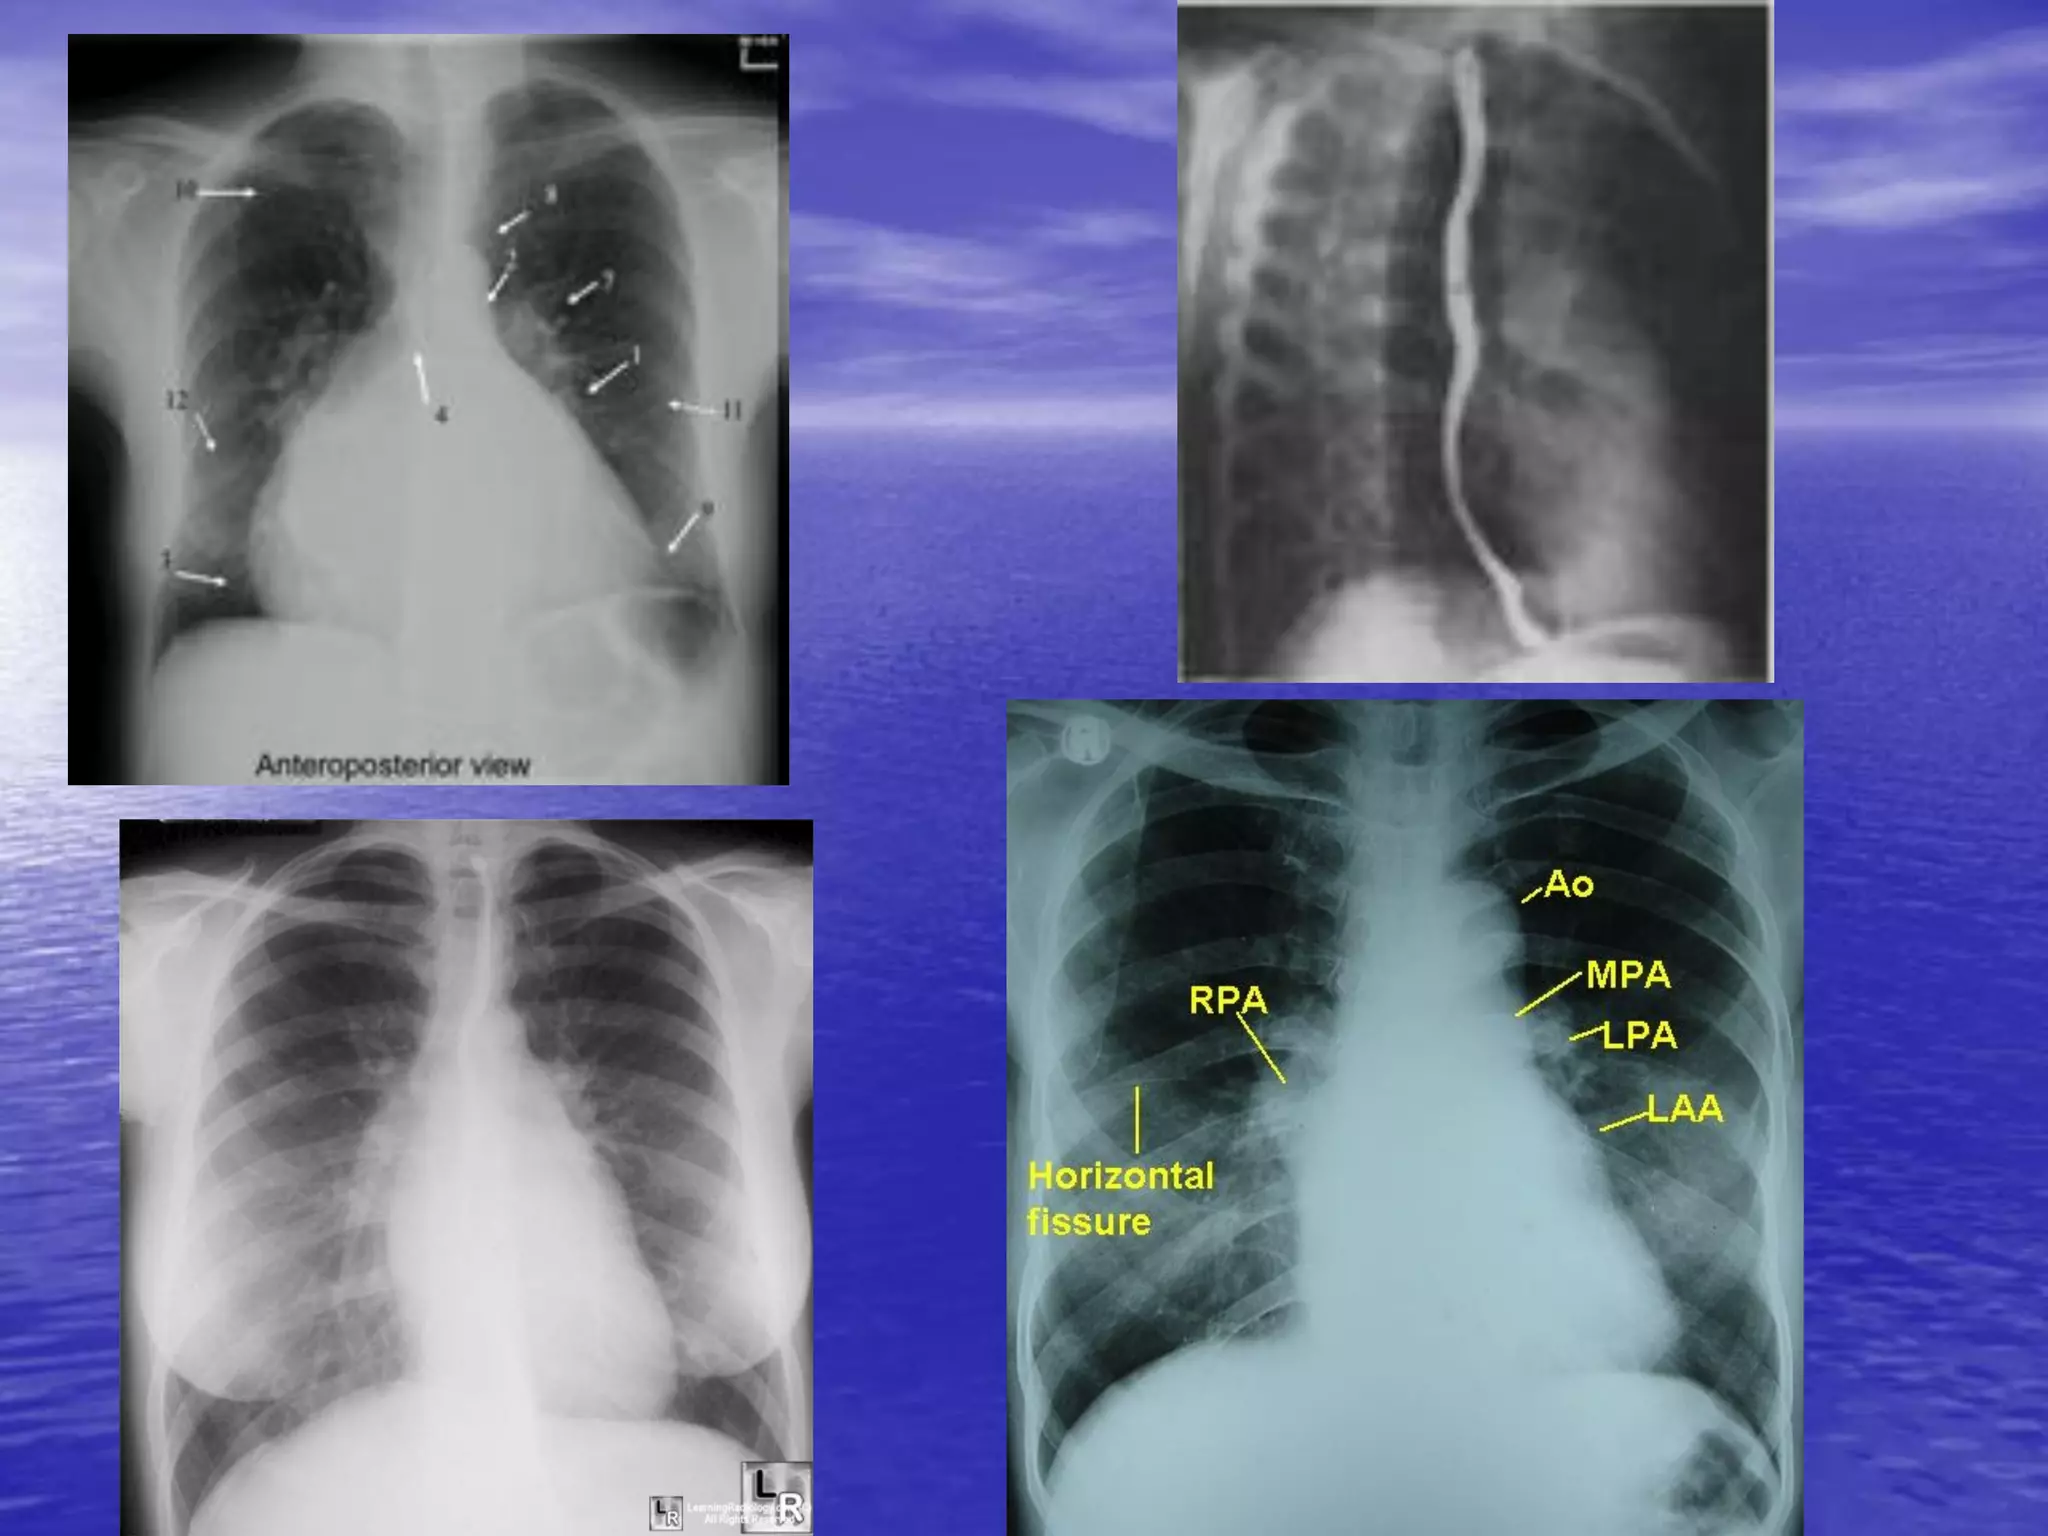

• Các cấu trúc giải phẫu tim1/ Nhĩ P

3/ TM chủ trên

5/ Tiểu nhĩ P

7/ Thất T

9/ Động mạch phổi

11/ Bóng hơi dạ dày 2/ Thất P

4/ TM chủ dưới

6/ Nhĩ T

8/ Động mạch chủ

10/ Tiểu nhĩ T

12/ Cột sống ngực

Giải phẫu tim/ XQ ngực bình thường – bệnh lý • Các cấu trúc giải phẫu tim1/ Nhĩ P 3/ TM chủ trên 5/ Tiểu nhĩ P 7/ Thất T 9/ Động mạch phổi 11/ Bóng hơi dạ dày 2/ Thất P 4/ TM chủ dưới 6/ Nhĩ T 8/ Động mạch chủ 10/ Tiểu nhĩ T 12/ Cột sống ngực